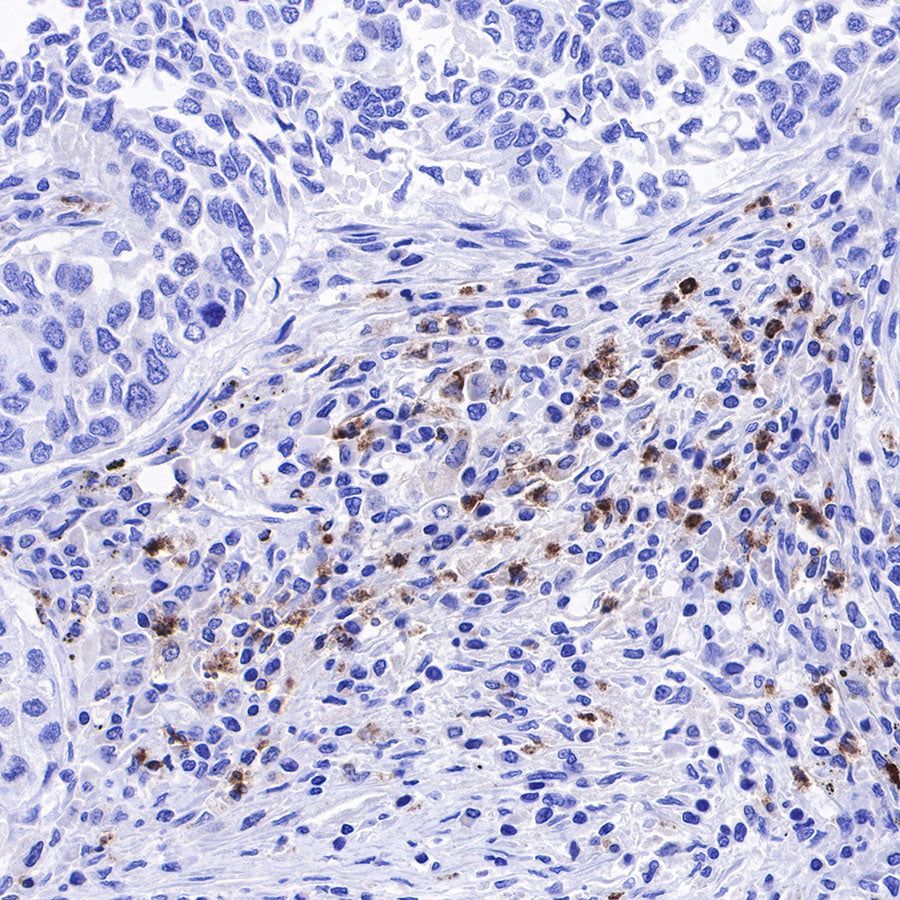

IHC shows positive staining in paraffin-embedded human tonsil. Anti-Lysozyme antibody was used at 1/100 dilution, followed by a HRP Polymer for Mouse & Rabbit IgG (ready to use). Counterstained with hematoxylin. Heat mediated antigen retrieval with Tris/EDTA buffer pH9.0 was performed before commencing with IHC staining protocol.